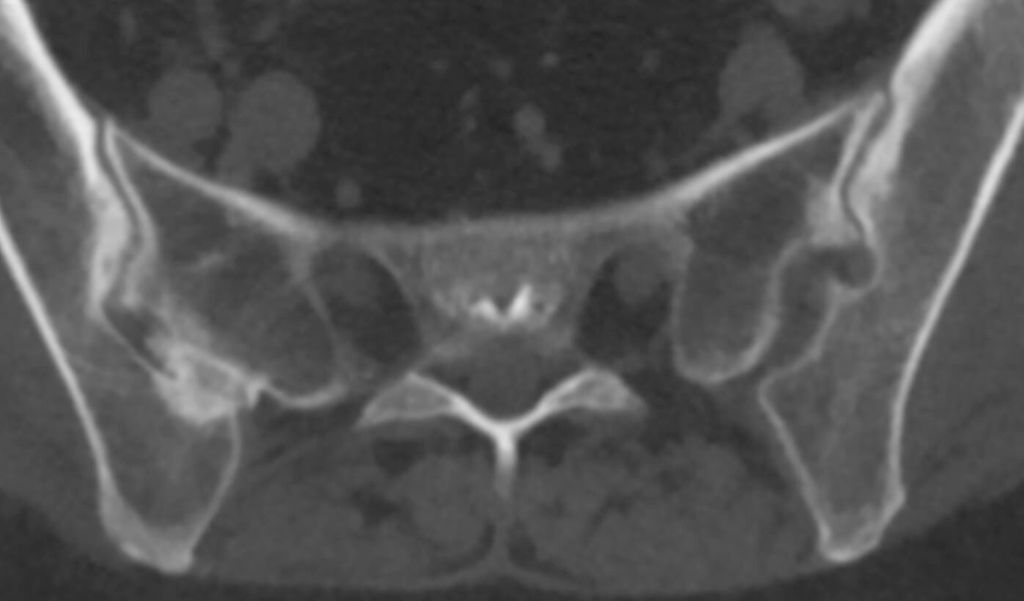

Abb. 2: Computertomografie: überlagerungsfreie CT-Darstellung der knöchernen Veränderungen an den Sakroiliakalgelenken mit Sklerosierungen, Erosionen und Ankylosen

Auch die CT hat als röntgenstrahlenbasiertes Verfahren ihre Stärke im Bereich der knöchernen Strukturen, mit dem Vorteil einer überlagerungsfreien Darstellung (Abb. 2). Die Auflösung ist für die meisten Fragestellungen ausreichend, erreicht jedoch nicht das Niveau von Röntgen-Detailaufnahmen oder hochauflösenden Ultraschalluntersuchungen. Die CT ist prinzipiell auch für großräumige Untersuchungen geeignet, wobei die erhebliche Strahlenbelastung als limitierender Faktor zu bedenken ist. Die Verfügbarkeit ist allgemein gut, und die Untersuchungsdauer ist kurz. Allerdings ist eine CT mit einem gewissen geräte- und untersuchungstechnischen Aufwand verbunden und dementsprechend teuer.

Zur genaueren Abklärung wurde eine CT durchgeführt. Dabei zeigten sich deutliche erosive Veränderungen, jedoch kein Hinweis auf eine Fraktur (Abb. 6). In Zusammenschau mit der Klinik bei zusätzlich vorliegenden Hautveränderungen palmar und plantar wurde die Diagnose eines SAPHO-Syndroms (Synovitis, Akne, Pustulosis, Hyperostosis und Osteitis), einer Form der seronegativen Spondylarthritiden, gestellt.